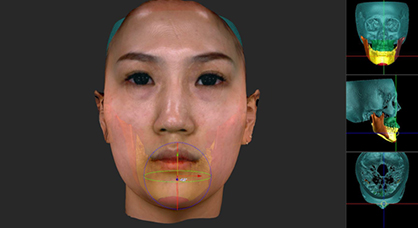

삼차원적 안모 분석을 위한 최첨단 시스템

삼차원 영상 채득3D Scanning

LED beam을 이용하는 원리로

방사선노출이 없습니다.

얼굴 외형 분석Facial Contour Analysis

스캐너로 얻은 영상 정보를 토대로

얼국 각 부위의 상대적 크기 및 비율을 분석합니다.

이차원 진단Surgical Treatment Objective(STO)

삼차원 영상과 방사선 사진을 중첩하여

수술 계획을 세웁니다.

삼차원 가상 수술3D Virtual Surgery

삼차원 영상과 CT영상을 이용하여 가상수술을 시행합니다.

수술 후 변화되는 안모를 미리 예측할 수 있습니다.